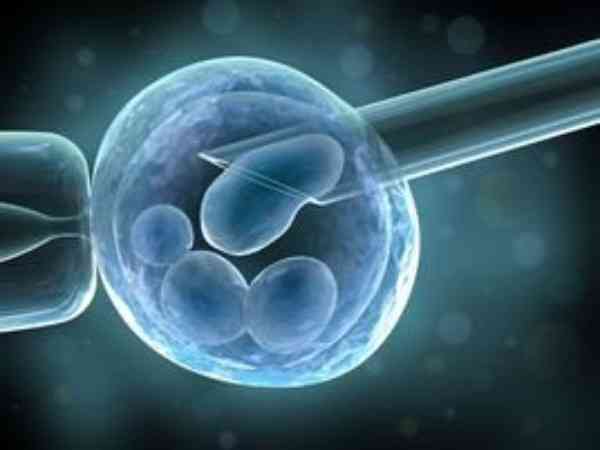

试管期间吃DHEA的原因盘点,改善卵巢只是作用之一

试管婴儿雄性激素药物中最常使用的就是DHEA,通过服用DHEA帮助女性补充雄激素,从而调节女性的卵巢功能,DHEA中的雄激素含量并不算很高,而且是一种保健药品,在服用时一般不会对人体造成太大影响,不过服用时也要注意用法和用量。

天津医科大学总医院试管婴儿攻略,需不需要染色体检查速览

天津医科大学总医院可进行夫精人工授精技术、常规体外受精-胚胎移植技术、卵胞浆内单精子显微注射技术,一般来说做试管前期检查都要做染色体的,通过染色体检查可以发现是否存在染色体遗传疾病,若是夫妻双方染色体属于正常,可以通过一代或者二代试管婴儿助孕,如果异常,可以选择三代试管助孕,一代二代试管是不能进行染色体筛查的。